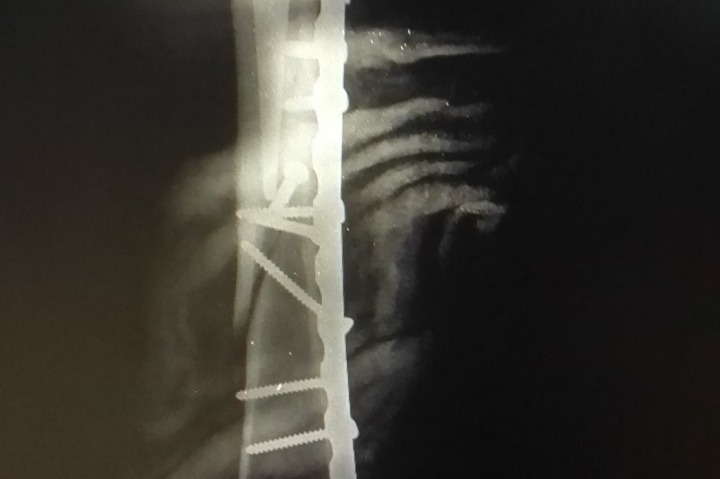

Gisela Briceño es una mujer luchadora, a quien le ha tocado superar varios desafíos de salud a lo largo de su vida. Uno de los más importantes fue el cáncer de mama con metástasis al que sobrevivió hace 11 años. Las secuelas de las sesiones de fuertes quimioterapias fueron muchas, entre ellas el notorio debilitamiento de sus huesos. Hace 5 años hubo que colocarle una prótesis de cadera debido a una fractura. En estos momentos sufrió una caída, la cual le provocó una segunda fractura en el fémur de la misma pierna lesionada anteriormente, por esta razón hubo que operarla de emergencia y colocar una placa en el hueso.

Gisela Briceno is a fighter in crisis-ridden Venezuela. She fought cancer 11 years ago and beat it. Since then, however, she has had to cope with the weakening of her bones as a result of chemotherapy. Five years ago she fell and broke her leg, leading to a hip replacement. Currently, she’s recovering from a second leg surgery due to a recent bad fall treated in an emergency procedure. As a cancer survivor, Venezuelan insurance companies wouldn’t insure Gisela, so we kindly appeal to your generosity to help us cover part of her expenses, which include medical supplies and care, both in scarcity due to the country’s economic crisis, now exacerbated by COVID-19. Every little bit will go a long way in Gisela’s fight to a full recovery.